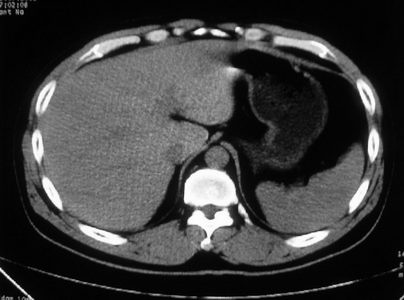

男,体查发现右肝低密度,右肾高密度结节影。高密度ct值92hu,囊肿?

肝右叶囊肿或血管瘤?右肾高密度囊肿。建议增强。

肝右叶圆形低密度灶,考虑囊肿或血管瘤,建议ct增强检查;右肾包膜下高密度圆形灶,考虑:囊肿并出血